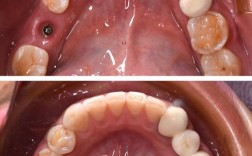

安装基台和牙冠阶段:

- 基台安装: 在骨结合完成后,医生会再次切开牙龈,暴露种植体顶部,安装一个连接基台,这个操作通常也需要局部麻醉,过程中不会疼,术后可能会有轻微的牙龈不适或肿胀,但疼痛感非常轻微,通常不需要止痛药。

- 戴牙冠: 这是最接近你问题“带牙冠”的阶段。

- 取模: 在安装永久牙冠前,医生需要取牙齿模型,这个过程完全无创,不会引起疼痛。

- 试戴和粘接: 当最终制作的牙冠安装到基台上时,这个过程是无创的,医生会调整咬合,确保牙冠与对颌牙齿、邻牙以及种植体基台都合适。

- 戴牙冠后: 绝大多数情况下,戴牙冠本身不会引起疼痛,你可能会有以下感觉,但不属于疼痛: